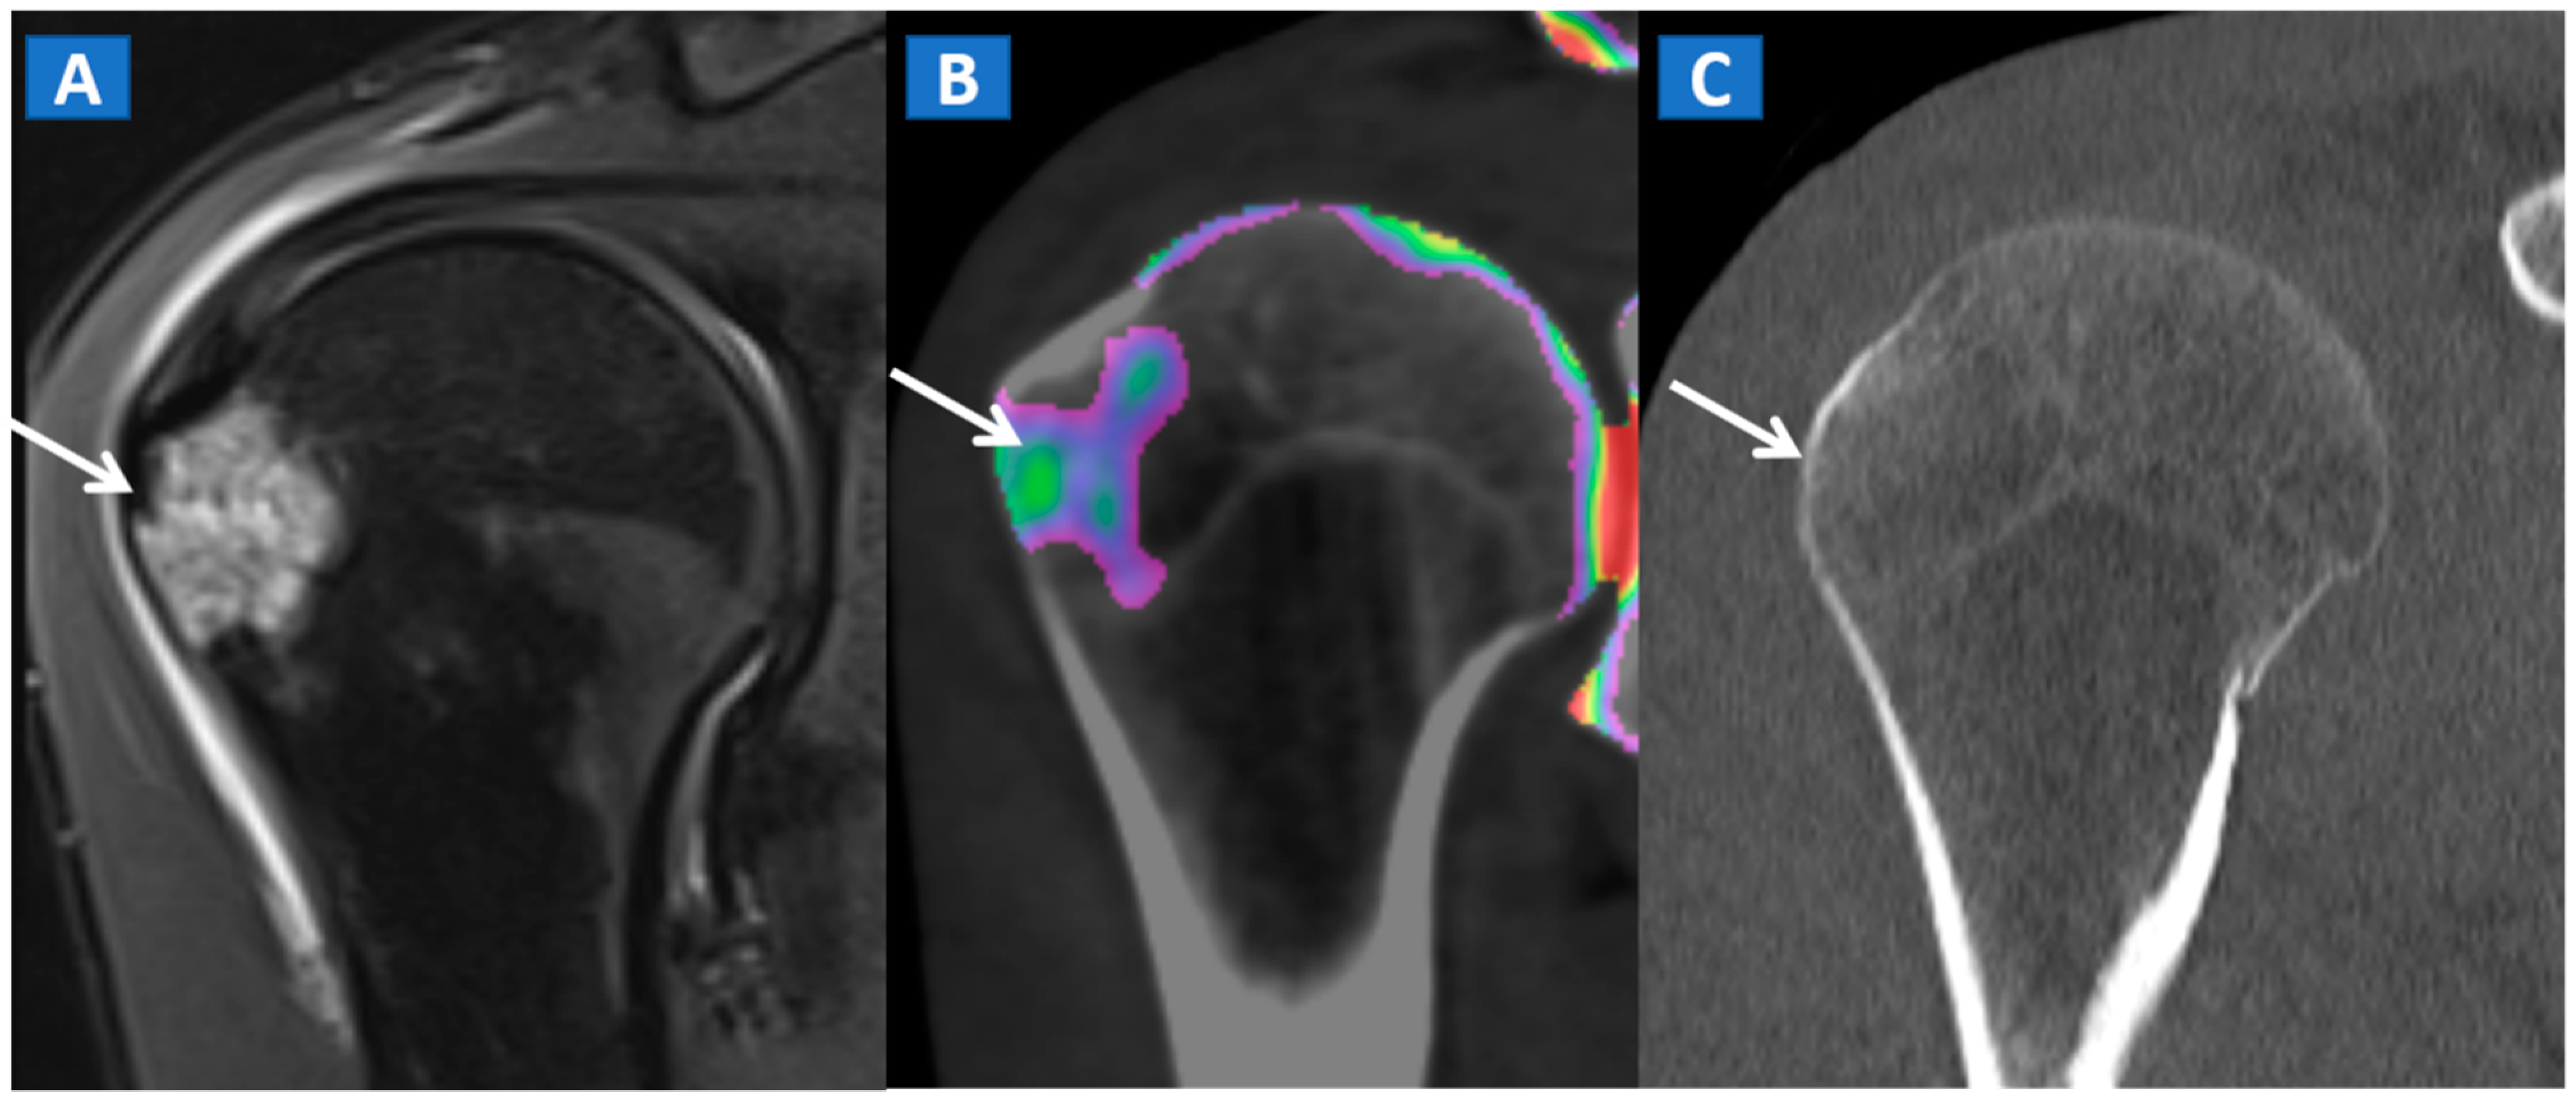

In the post-traumatic shoulder, DECT can identify BME of the humeral head, even in the absence of cortical fractures (Figure 8). Furthermore, in cases of anterior dislocation, CT images can be used for diagnosing Hill-Sachs and bony Bankart lesions.

Figure 8.

A 35-year-old male with traumatic BME of the humeral head. On the coronal STIR MRI image (A), post-traumatic BME of the humeral head is depicted as a hyperintense signal in the subcortical area (arrow). The presence of BME is confirmed on the 2D DECT coronal 1 mm reconstructed image (B) (arrow). The high resolution 1 mm coronal CT image with bone window (C), rules out the presence of cortical fractures.